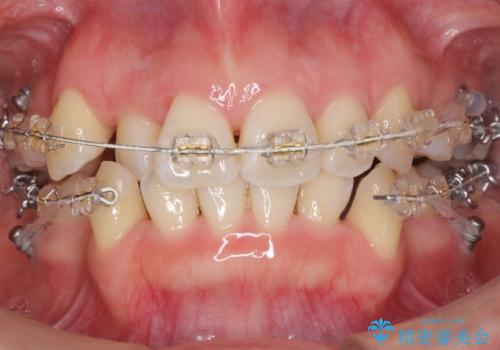

- 矯正装置

- 審美装置

- 治療期間

- 2年3ヶ月

- 前歯のがたつきと正中のずれを主訴に来院。

小臼歯を4本抜歯しています。